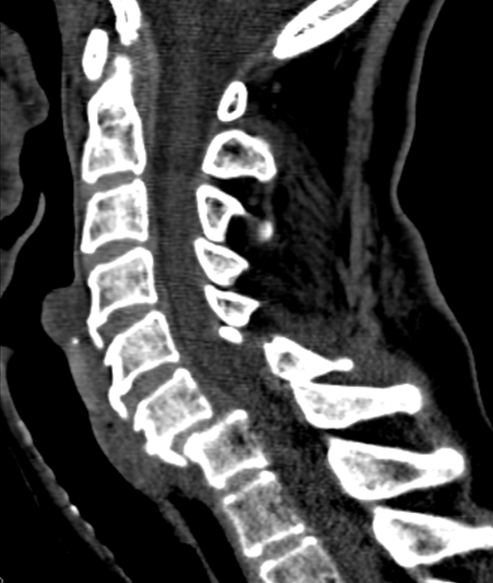

fell down stairs, weakness of elbow extension & wrist flexion

decreased pain sensation in index & middle fingers

typically occurs with forced flexion of cervical spine (ie, falling onto flexed neck) → single facet disloicated, radiculopathy

this case is c7 radiculopathy